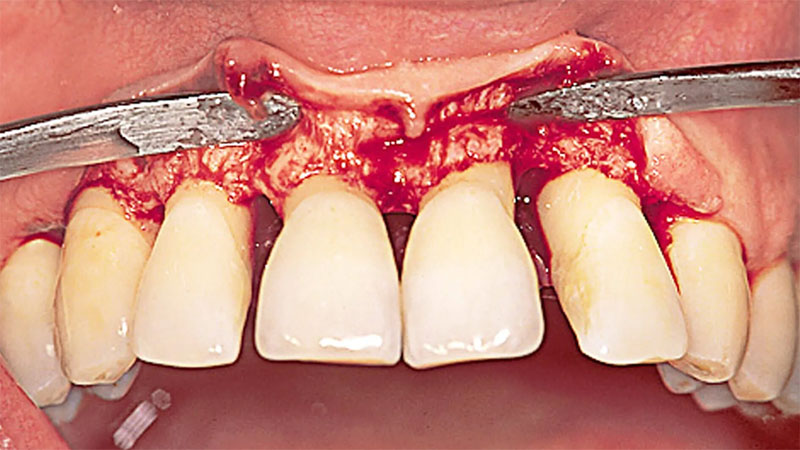

اما عمل لیفت لثه همیشه به این اندازه ساده و بی دردسر نبوده است. در گذشته لیفت لثه با تیغ جراحی انجام می شد. در ادامه نگاهی به این روش لیفت لثه می اندازیم.

لیفت لثه با جراحی

لیفت لثه به کمک تیغ جراحی می تواند خطوط کج لثه و همین طور لبخند ناموزون را صاف و موزون کند. در این روش جراح بافت اضافه لثه را نه با لیزر بلکه به وسیله چاقوی جراحی بُرش می زند و جدا می کند و در انتها کار به بخیه زدن می رسد.